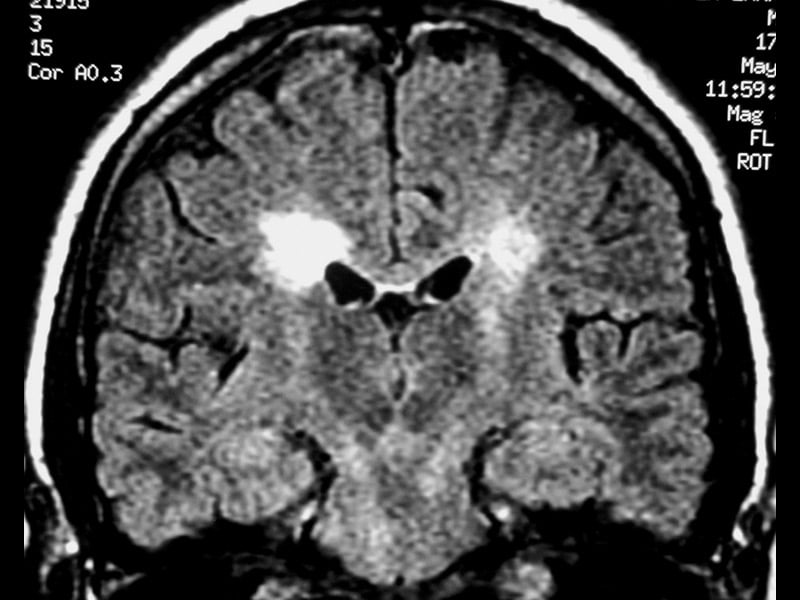

Демиелинизирующие заболевания мозга: МРТ изображения